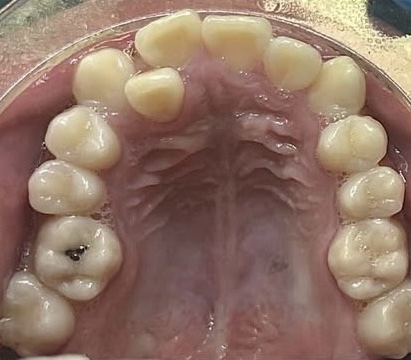

Crowding and constricted arch. Comprehensive orthodontic treatment was performed, and teeth alignment was restored.